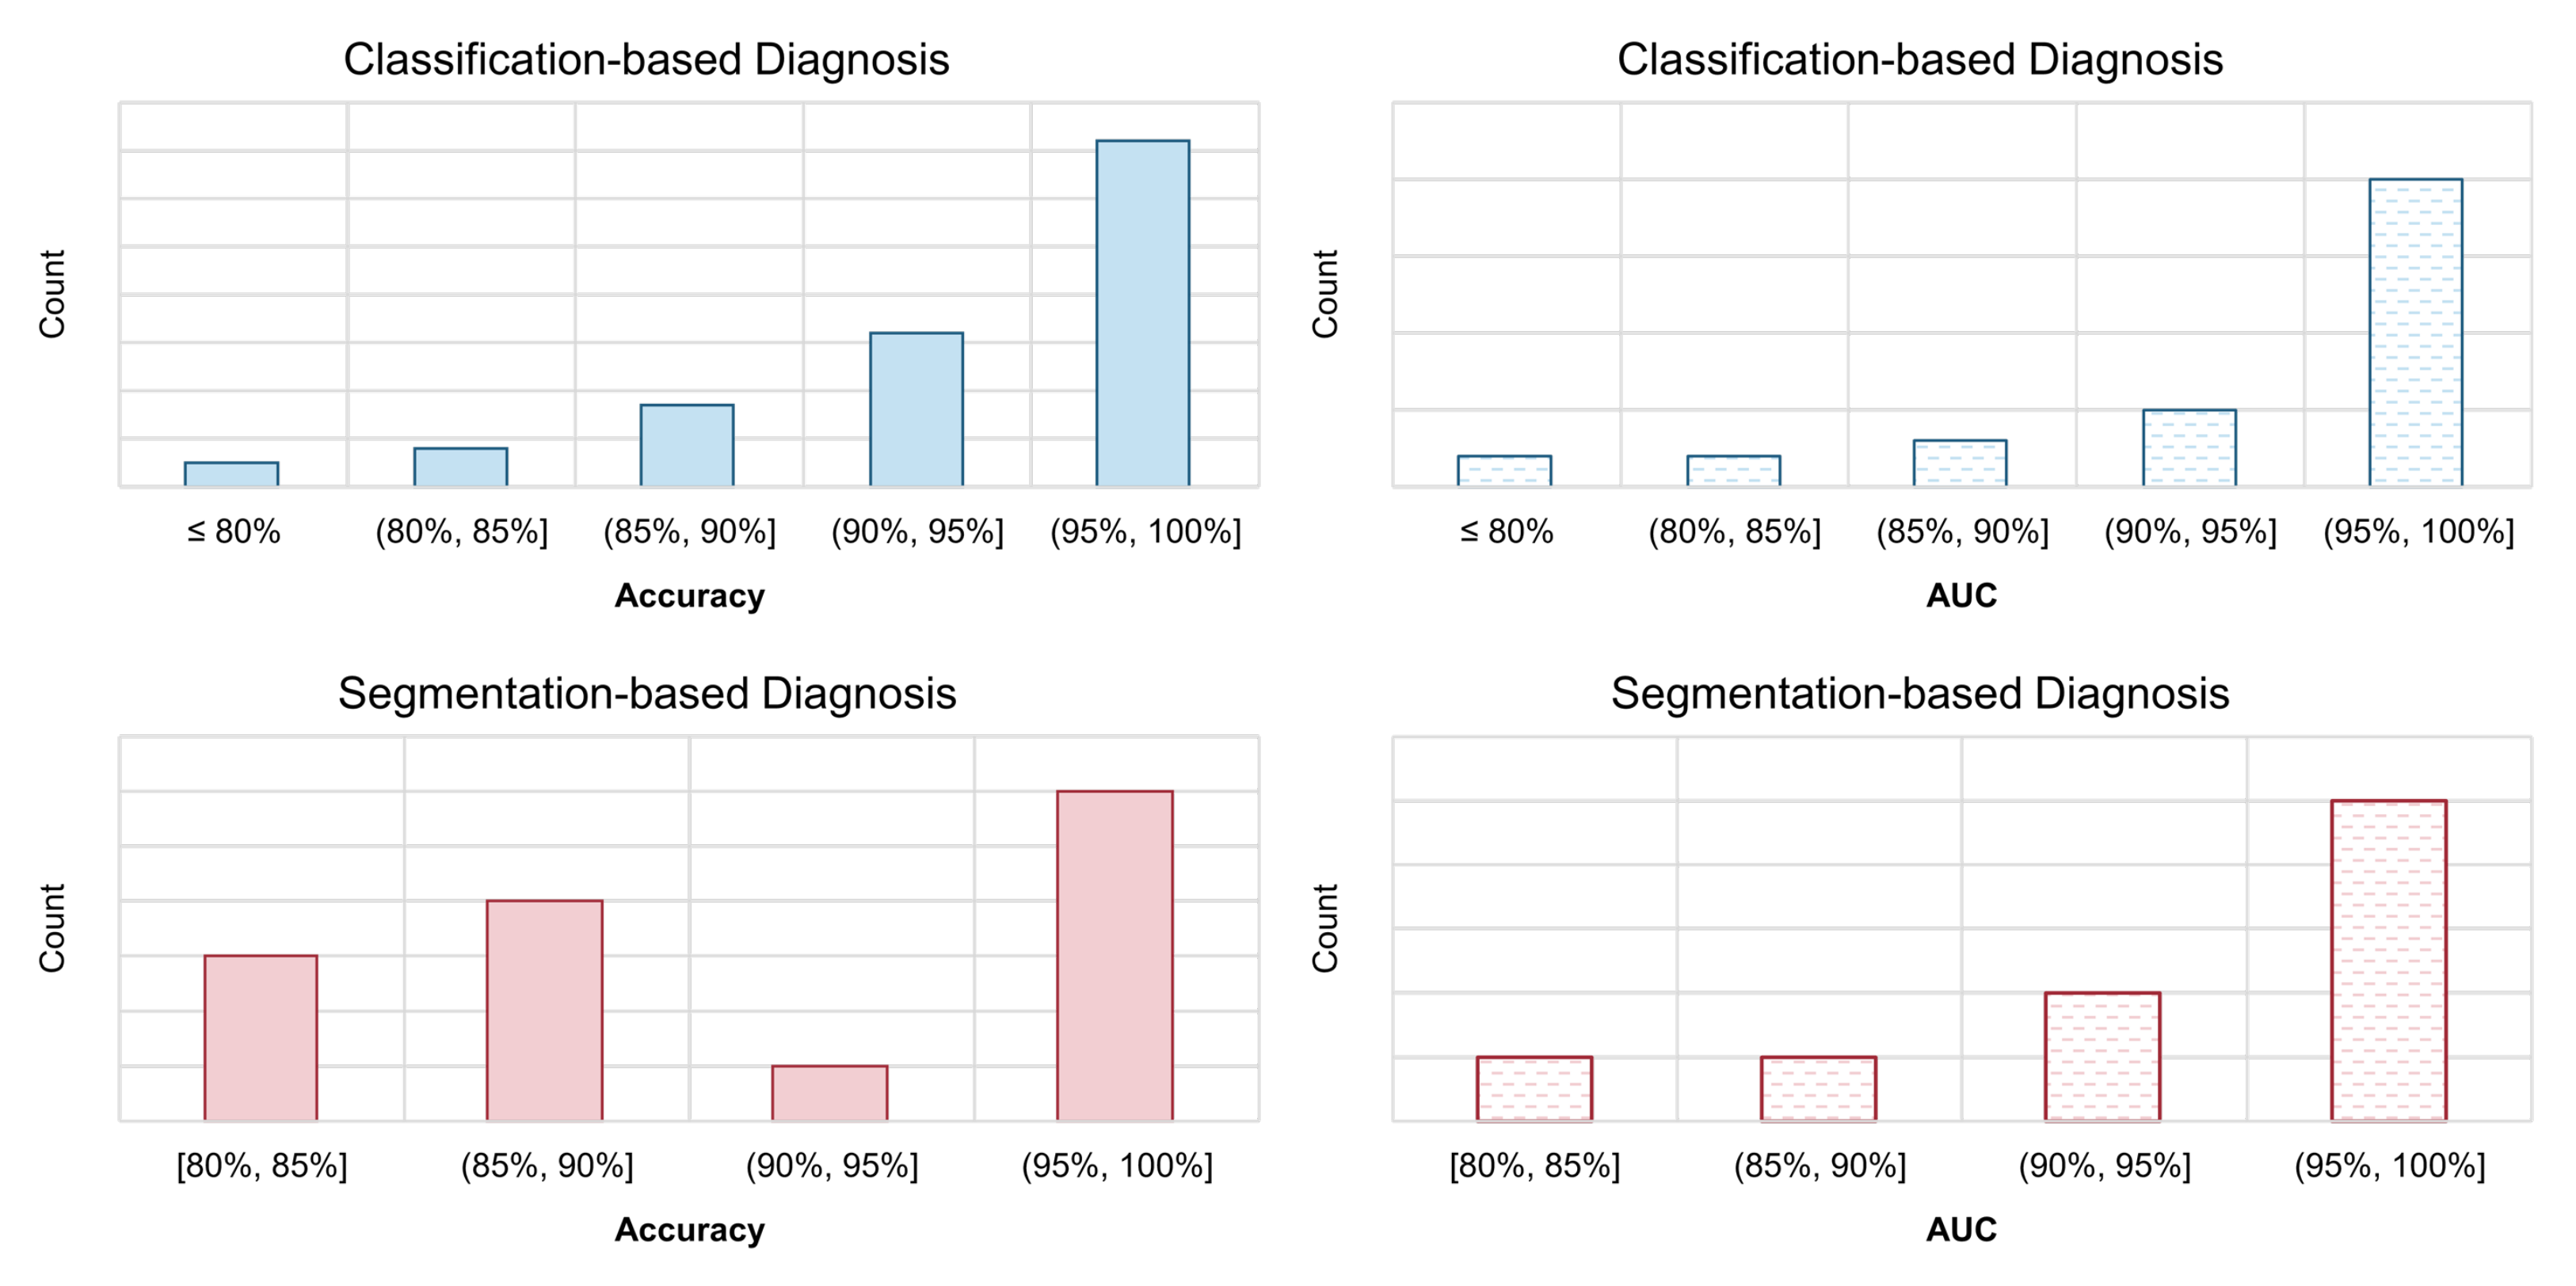

3.1. Image-Level Diagnosis: Classification-Based Models

3.1.1. Overview

3.1.5. Evaluation

3.2. Pixel-Level Diagnosis: Segmentation-Based Models

3.2.1. Overview

3.2.4. Evaluation